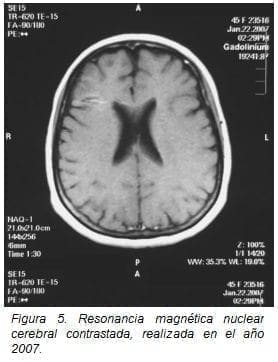

Los estudios de imagen datan desde el inicio de su cuadro clínico: en 1990, se realizó una tomografía axial computarizada cerebral y de médula espinal que se reportaron como normales; en el 2013 se practicó estudio de resonancia magnética cerebral no se observan lesiones de espectro E. múltiple (figuras 4 y 5).